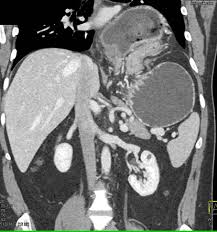

Ct Images Of Two Patients With Either Water Only Or Telebrix Gastro As Download Scientific Diagram